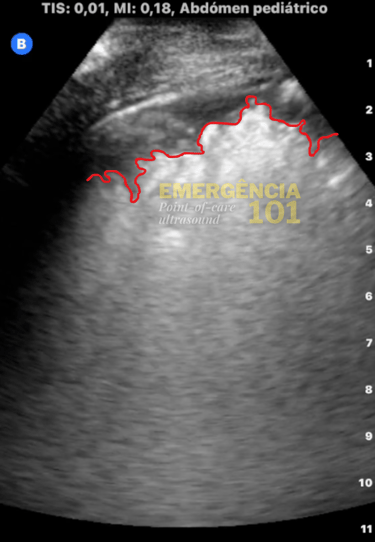

Figura 5a. Consolidação subpleural não-translobar em paciente com pneumonia. "Shred sign". Acervo pessoal do autor.

Figura 5c. Irregularidade pleural do "shred sign" para comparação com a tomografia (observação: pacientes diferentes). Acervo pessoal do autor.